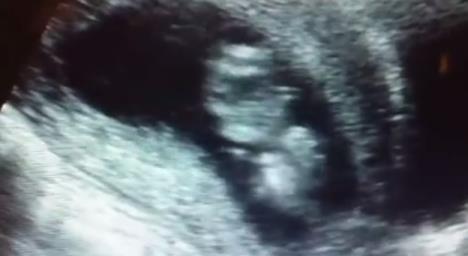

Tako je krenula i ova majka, ali njena beba odlučila je da neće da ćuti! Pre samog abortusa majka je išla na ultrazvuk, a njena beba, stara samo 11 nedelja u tom trenutku (kao da je znala što treba da uradi) odlučila je da pokaže majci da je živa.

Počela je da skače u majčinoj utrobi a ona je ostala u šoku. Kada je videla ovaj snimak i svoju živu i energičnu bebu shvatila je da je njeno dete puno života koji ne sme da ugasi, pa je od abortusa odustala.

This baby was saved at a pregnancy resource center when his mother chose life after seeing this ultrasound. We discovered later in the pregnancy this baby was a BOY! For everyone who is wondering what can be seen on an ultrasound of a 1st trimester baby. Enjoy!11 weeks 4 days old baby. So much energy & life!!! Precious baby =)